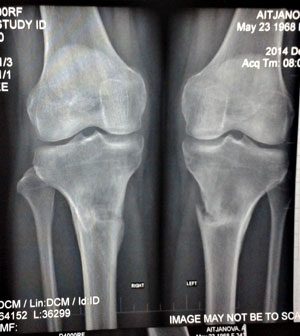

Здравствуйте, Алмагуль! Спасибо за поздравления! Очень рады за Вас, ножки супер, мы гордимся своей работой - таким результатом! Нагрузка Вам разрешена без ограничений, рентген отличный! Всё у Вас железно, не переживайте, живите полной жизнью, на зависть всем!Здравствуйте, Николай Николаевич и Наталья!

Чувствую себя хорошо, ноги не беспокоят, после снятия аппарата еще два месяца носила бандаж для страховки, обувь ношу только на низком.

24-того декабря делала рентген,если есть необходимость, то я вышлю его по почте на следующей неделе.

Хотела бы узнать Ваши комментарии по поводу рентгена. Еще хотела бы узнать можно ли увеличить физ. нагрузки,носить каблуки?